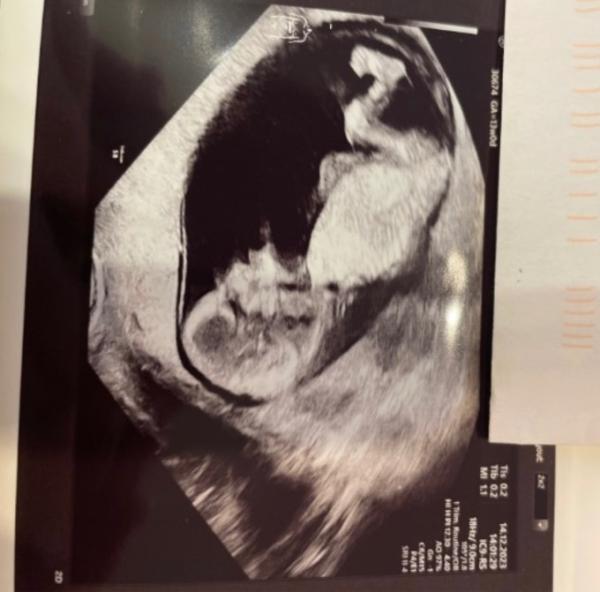

Bei der letzten Untersuchung war alles prima. Die Prinzessin wächst und ist munter. Die Plazenta ist diesmal an der Hinterwand, was mich auch beruhigt.

Sie hat ihren kleinen Kopf bei der Untersuchung richtig nach unten gepresst, so konnte man quasi kein schönes Bild machen. Aber halb so wild, solange ich weiß das alles gut ist.

Bild ist vom Fein Ultraschall letzten Donnerstag, das war 13+0